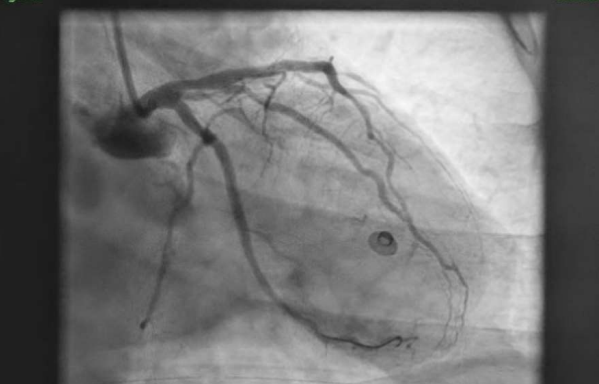

72 Year old male with no comorbidities, was brought to ER in a state of unresponsiveness since 1 hour. Initial evaluation revealed normal vitals signs, GCS: E1V1M1, GRBS of 180mg/dL. ABG was also normal. He was intubated for airway protection. ECG changes (FIG1) were present as shown in the figure. ECHO done showed apical hypokinesia with LVEF 20%. He underwent a CT brain which revealed no acute infarct/ bleed. Troponin was elevated. He was taken up for primary PCI which revealed LAD and LCx having 100% thrombotic occlusions (FIG 2) which were successfully treated by 1X DES in LAD and 1xDES in LCx achieving TIMI 3 flow (FIG3) . Patient was extubated the following day as he regained consciousness with no end organ damage or shock. Timely intervention and inclusion of two arteries as culprit vessels, with such peculiar presentation as well as the ECG changes makes it a case of rarity. It also signifies the importance of treating the condition on an emergent basis to aid in complete recovery.

FIG 2 : CORONARY ANGIOGRAM SHOWIN LAD AND LCX 100% THROMBOTTIC OCCLUSION